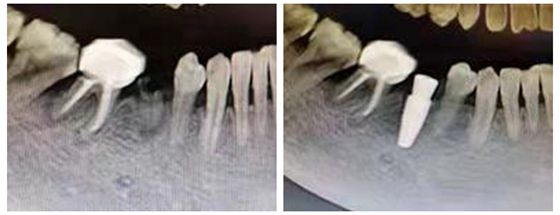

根据易大姐目前的病情,朱彬医师请口腔外科向峰医师会诊,共同为易大姐制定了合适的治疗方案:首先针对口内多颗坏牙再次填充治疗,同时拔除右下方的残牙断根,植入人工牙根。朱彬医师为患者完成了口内坏牙的充填治疗后,向峰医师在不到一小时的时间里将烂牙根替换成人工牙根,牙龈仅缝合2针,坏牙填充无缝与人工牙根植入无缝连接,一气呵成。期间易大姐未有任何疼痛和不适感。3个月后,易大姐便可以任意食用美食了。

向峰医师介绍,将口内不能保留的患牙即刻拔除,然后即刻植入种植体大大缩短了拔牙及镶牙的治疗时间,最重要的是避免了因拔牙后出现的骨吸收,为植入种植体保留了牙槽骨的高度和宽度。此次种植也充分利用牙龈的缺损区将愈合基台接入口腔,避免了种植的2期手术愈合基台的接入,一次性解决多个问题。